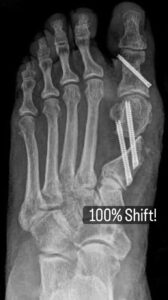

There is a lot of media these days about doing minimal incision bunion surgery, but patients should review our bunion and minimally invasive surgery services before choosing a procedure. Do not be a victim of the hardware doctor, and meet Dr. Singh to learn about his approach to true minimal incision correction. They think this is minimal incision. They make a small incision. Then they insert these large screws. Sometimes they insert screws and plates. This is not minimal incision. This is totally criminal. Who would want to have such a procedure done. Look at the second picture. This is a bunion. Who would want such correction done to them. Look at the third picture. How do you think the bunion is going to even heal? Stay away from the surgeons that profess minimal incision surgery using these types of hardware. Do yourself a favor and educate yourself.